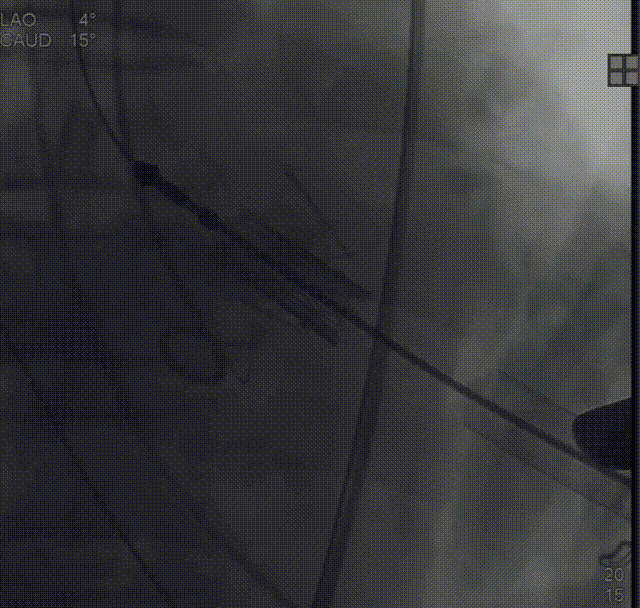

经股动脉送入猪尾导管,行根部造影:

定位件入窦后造影:

降落瓣膜件,完成释放:

复查根部造影,未见明显反流: